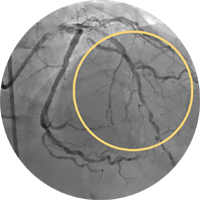

Внутристентовый рестеноз в левой передней нисходящей артерии: ко-регистрация данных с iFR и ВСУЗИ, лазерная атерэктомия, использование баллона с лекарственным покрытием и стентирование.

Хроническая тотальная окклюзия правой коронарной артерии. Изображение предоставил Крейг Томпсон, врач.